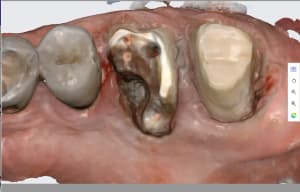

Capture d'écran 2026-03-20 143726.jpg